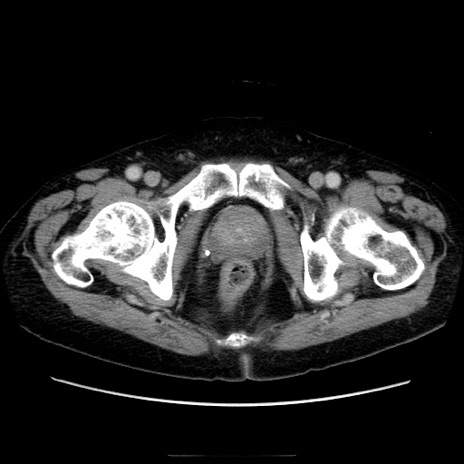

症例21(横断像)

【症例】70歳代男性

【主訴】腹痛

【現病歴】肝硬変・肝細胞癌にてかかりつけの方。約9時間前に食後より腹痛出現。症状が徐々に増悪し、嘔吐出現したため来院。

【既往歴】肝硬変、肝細胞癌(RFA、TACE後)

【身体所見】意識清明、表情苦悶様、BT 36℃、BP 129/78mmHg、P 88bpm、SpO2 97%(RA)、右上腹部から心窩部にかけて圧痛あり、反跳痛なし、筋性防御あり。

【データ】WBC 5800、CRP 0.16